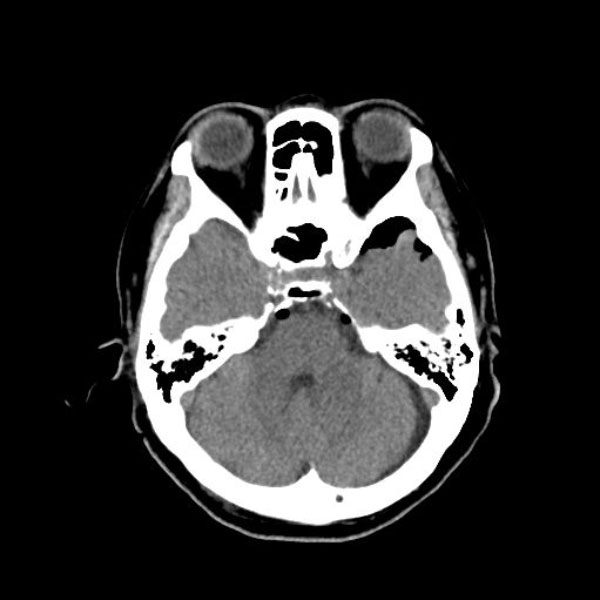

手術前

(MR1)

手術後

(CT)